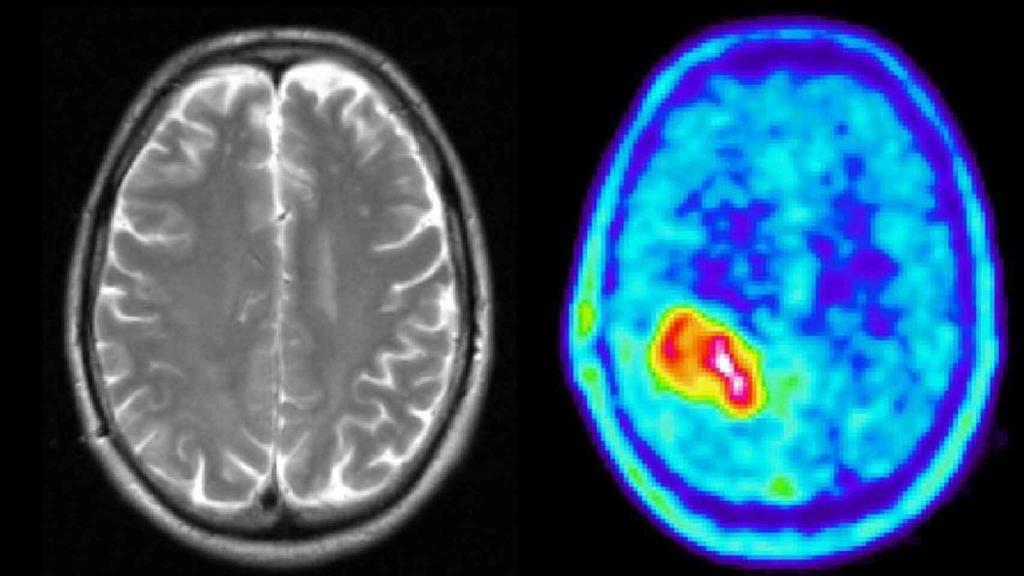

Una prueba diagnóstica muestra un tumor cerebral.